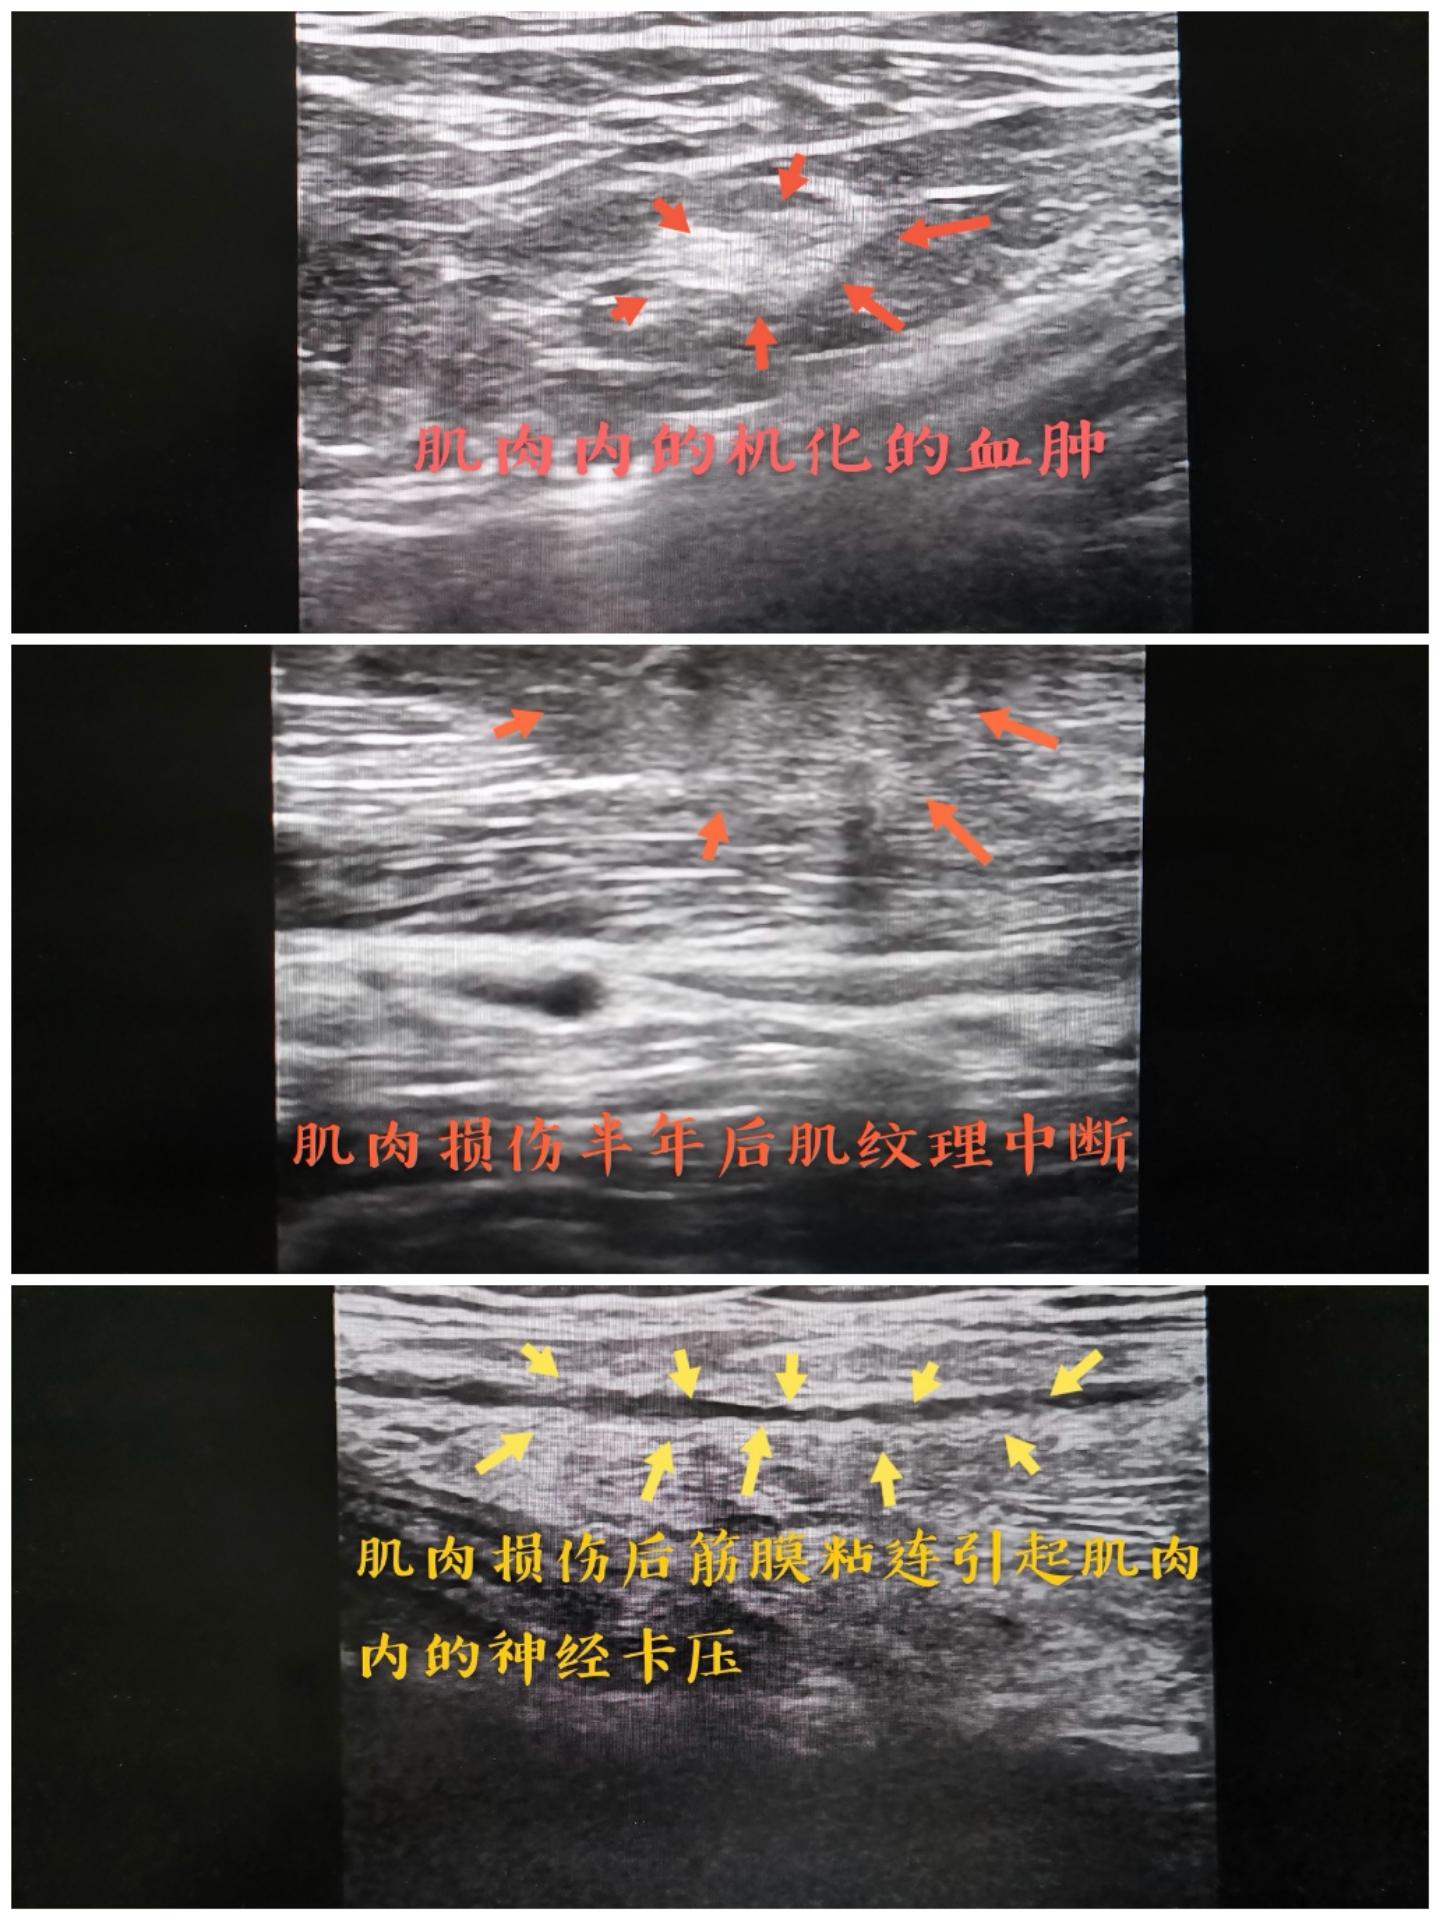

接诊黄先生后,吴礼平主任医师仔细询问病史认真做体查后,联系了超声二科的鲍觅夏医师为其做了超声引导下的治疗,鲍觅夏仔细为其做了检查,超声下显示黄先生腓肠肌外侧头有机化的血肿,肌肉纹理不清,腓总神经卡压。两人认真讨论治疗方案,松解了粘连的肌肉与神经,经治疗后症状明显改善。